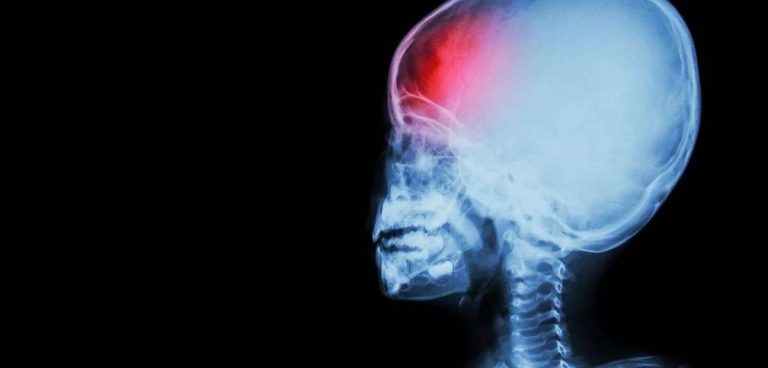

تعد إصابات الرأس أحد أكثر أسباب الإعاقة والموت شيوعًا عند البالغين. يمكن أن تكون الإصابة خفيفة مثل نتوء أو كدمة أو قطع على الرأس أو يمكن أن تكون معتدلة إلى حادة في طبيعتها بسبب ارتجاج أو جرح عميق أو جرح مفتوح، عظام (جمجمة) مكسورة أو من داخل نزيف وتلف الدماغ.

إصابة الرأس هي مصطلح واسع النطاق يصف مجموعة واسعة من الإصابات التي تحدث في فروة الرأس والجمجمة والدماغ والأنسجة والأوعية الدموية الأساسية في الرأس. يشار أيضًا إلى إصابات الرأس على أنها إصابات في الدماغ وهذا يتوقف على مدى صدمة الرأس.